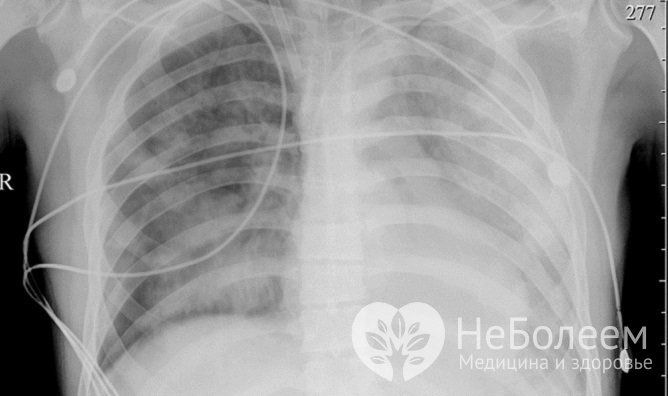

Наиболее серьезным проявлением аденовирусной инфекции у детей и взрослых является аденовирусная пневмония. Обычно она возникает на 3-5 сутки болезни, только у детей первых лет жизни аденовирусная инфекция может сразу манифестировать воспалительным процессом в легочной ткани. Симптомами аденовирусной пневмонии являются:

Аденовирусная пневмония может быть как мелкоочаговой, так и сливной, то есть охватывающей одновременно несколько сегментов легких.

Опасным осложнением аденовирусной инфекции является аденовирусная пневмония – на рентгенографии

Опасным осложнением аденовирусной инфекции является аденовирусная пневмония – на рентгенографииУ детей первых трех лет жизни аденовирусная пневмония нередко принимает тяжелое течение и сопровождается появлением пятнисто-папулезной кожной сыпи, формированием очагов некроза в коже, головном мозге и легких.